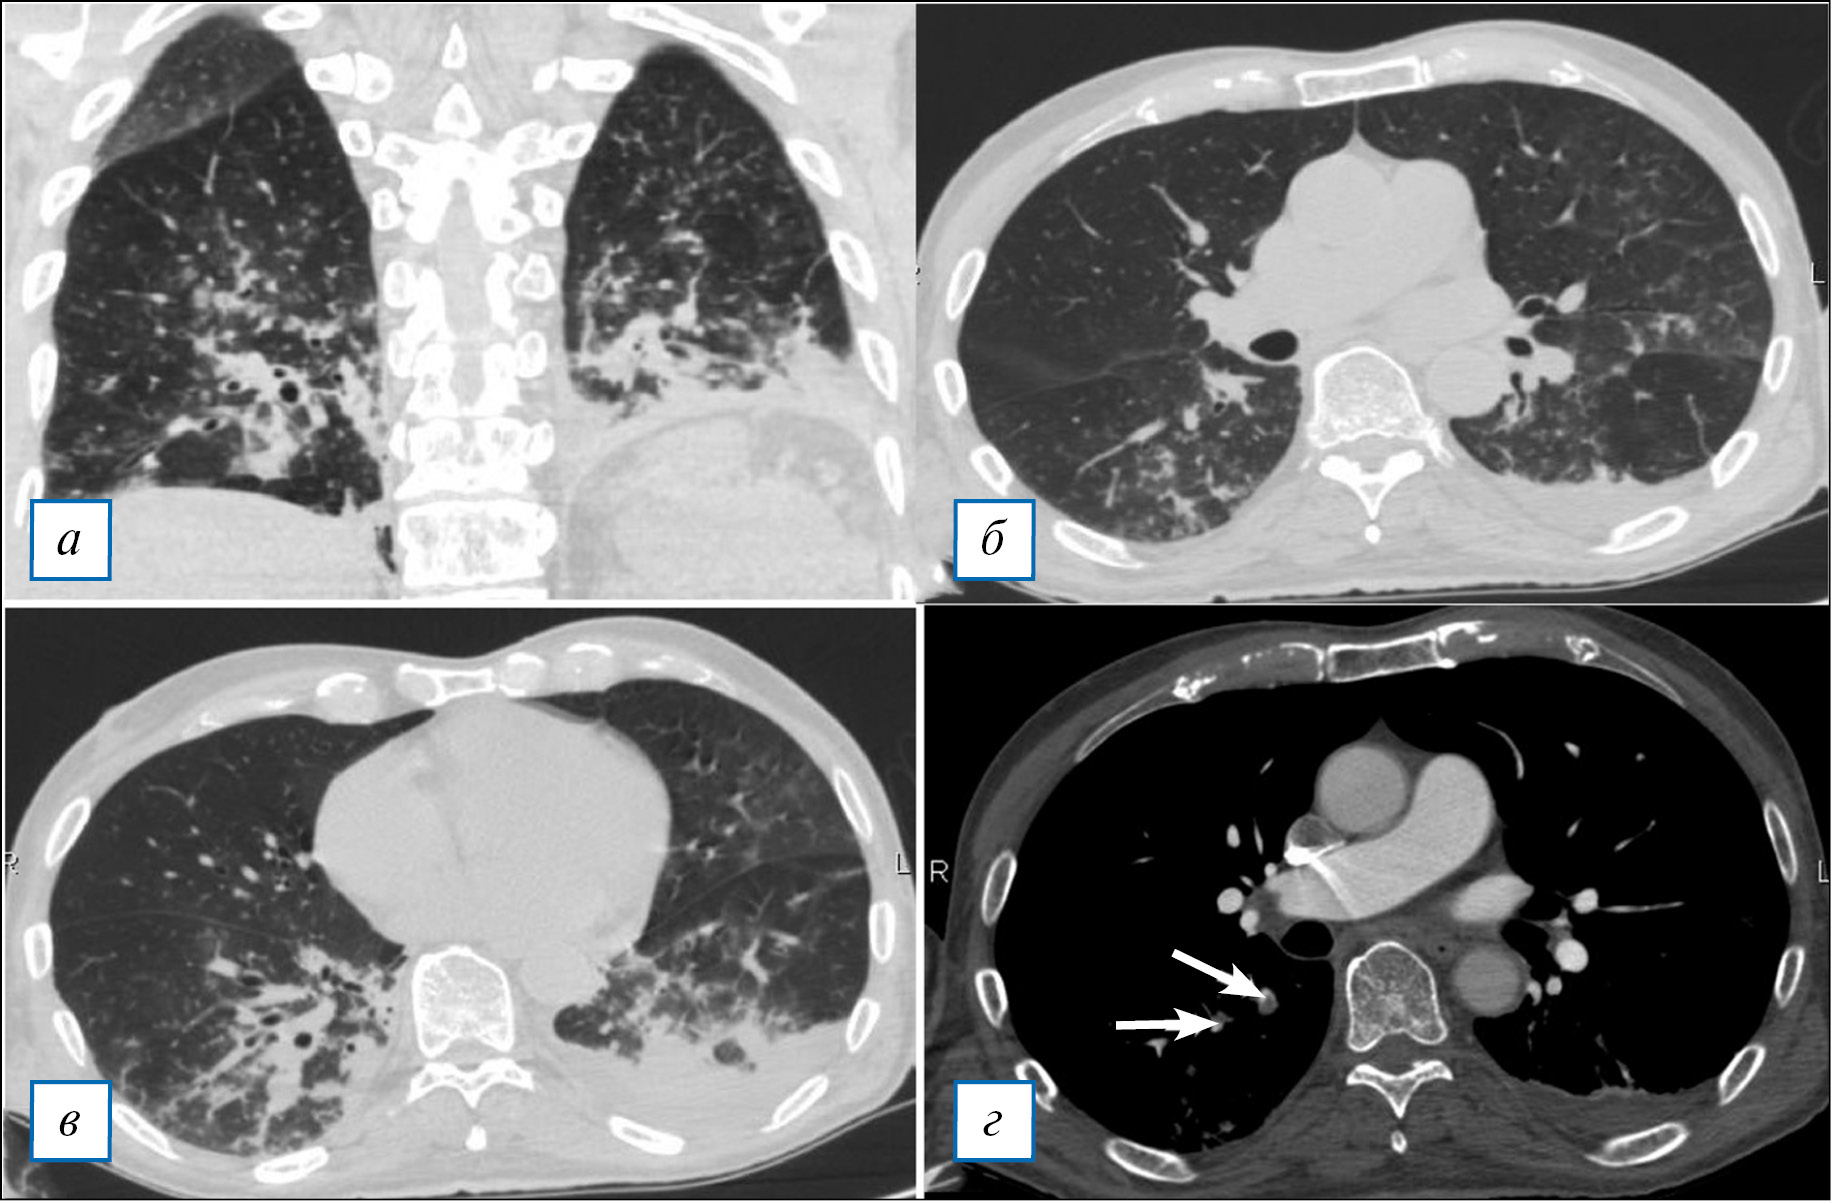

07.03.2021 вновь отмечено ухудшение общего состояния пациента: появились общая слабость, одышка при разговоре, редкий кашель, снижение сатурации SpO2 до 74%; температура тела оставалась в норме. В лабораторных показателях крови отмечено повышение лейкоцитов до 17,16х109/л, СРБ до 155,8 мг/л, прокальцитонинина до 4,48 нг/мл, D-димера до 1,114 мкг/мл, СОЭ до 40 мм/ч, а также снижение лимфоцитов до 0,46х109/л. Проведена компьютерная томография (КТ) органов грудной клетки: выявлена двусторонняя полисегментарная пневмония (рис. 2, а-в).

Рис. 2. Тот же пациент. Компьютерная томография органов грудной клетки: (а-в) — в обоих легких (в верхней доле левого легкого, в S2, S4, сегментах нижней доли правого легкого) определяются участки неоднородного снижения пневматизации легочной ткани по типу «матового стекла» и консолидации; (г) — ТЭЛА мелких ветвей (сегментарные ветви справа, показаны стрелками).

Fig. 2. The same patient. CT-scan of the chest: (а-в) — In both lungs (in the upper lobe of the left lung, in S2, S4, segments of the lower lobe of the right lung), areas of «ground glass» and consolidation are determined; (г) — Pulmonary embolism of segmental branches on the right (white arrows).

На следующий день была проведена КТ сосудов грудной полости с контрастным усилением, которая выявила тромбоэмболию ветвей легочной артерии (рис. 2, г). Выполнено дуплексное сканирование вен нижних конечностей: выявлен тромбоз глубоких вен обеих голеней в стадии начальной (слабовыраженной) реканализации без признаков флотации.

Острая воспалительная моторная аксональная полинейропатия (синдром Гийена-Барре), вызванная коронавирусной инфекцией SARS-CoV-2. Вялый тетрапарез с преобладанием в ногах, выраженным болевым синдромом и нарушением функции тазовых органов, тяжелого течения. Двусторонняя полисегментарная пневмония в стадии разрешения. Осложнение: тромбоэмболия мелких ветвей легочной артерии. Тромбоз глубоких вен нижних конечностей в стадии начальной реканализации.

Характерная клинико-рентгенологическая картина (интерстициальное поражение легких с феноменами «матового стекла» и консолидации, лимфопения и повышение СРБ), а также наличие специфических IgG и IgM к S-белку SARS-CoV-2 позволили поставить диагноз COVID-19, несмотря на отрицательный результат ПЦР на SARS-CoV2.